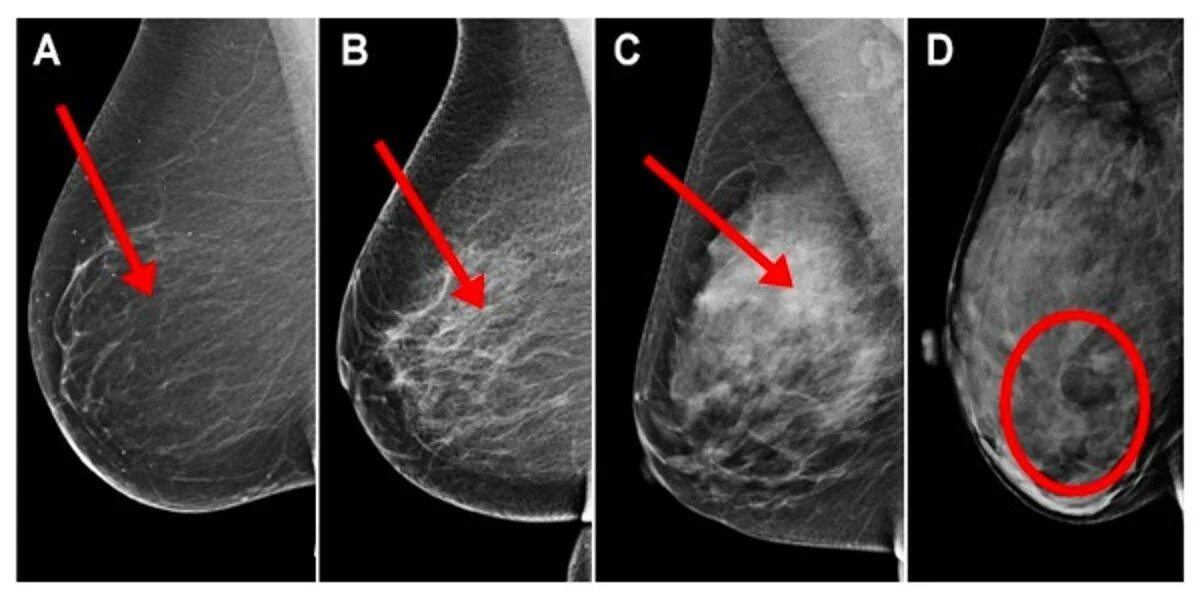

Тип строения молочных желез по acr